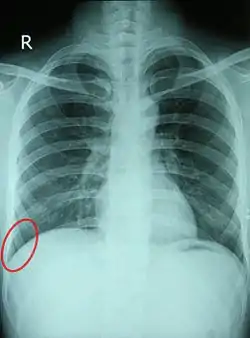

![]() Chest X-ray of a 30-year-old healthy man, with the costodiaphragmatic recess label in red ellipse | |

In anatomy, the costophrenic angles are the places where the diaphragm (-phrenic) meets the ribs (costo-).

Each costophrenic angle can normally be seen as on chest x-ray as a sharply-pointed, downward indentation (dark) between each hemi-diaphragm (white) and the adjacent chest wall (white). A small portion of each lung normally reaches into the costophrenic angle. The normal angle usually measures thirty degrees.

Pleural effusion

With pleural effusion, fluid often builds up in the costophrenic angle (due to gravity). This can push the lung upwards, resulting in "blunting" of the costophrenic angle. The posterior angle is the deepest. Obtuse angulation is sign of disease.

Chest x-ray is the first test done to confirm the presence of pleural fluid. The lateral upright chest x-ray should be examined when a pleural effusion is suspected. In an upright x-ray, 75 mL of fluid blunts the posterior costophrenic angle. Blunting of the lateral costophrenic angle usually requires about 175 mL but may take as much as 500 mL. Larger pleural effusions opacify portions of the hemithorax and may cause mediastinal shift; effusions > 4 L may cause complete opacification of the hemithorax and mediastinal shift to the contralateral side.